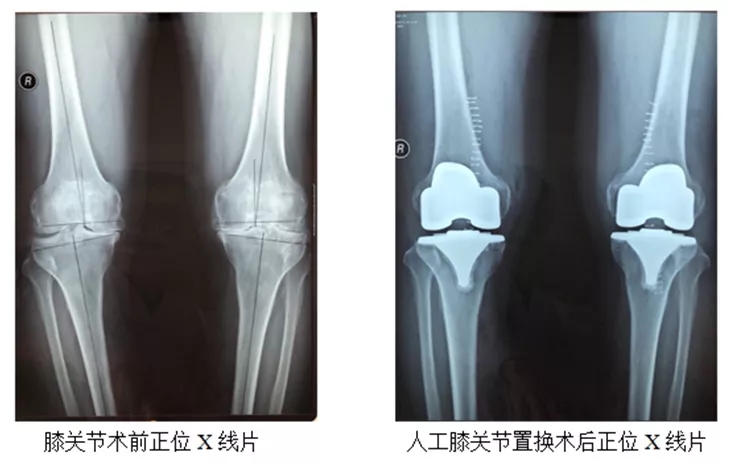

人工关节置换术:

人工关节置换术的治疗效果经过三十多年的临床实践,已经得到充分的肯定并已经发展成为一种可靠的治疗手段。人工关节置换术主要目的是缓解关节疼痛、矫正畸形、恢复和改善关节的运动功能。